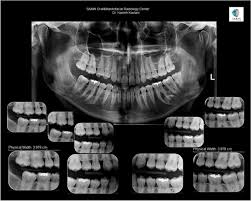

WHAT IS OPG IN DENTAL :-

OPG or Orthopentomogram is special x-ray of the lower face, teeth and jaw. An OPG is a panaromic view of x-ray of the lower face and jaw which displays allthe teeth of upper and lower jaw on a single film.